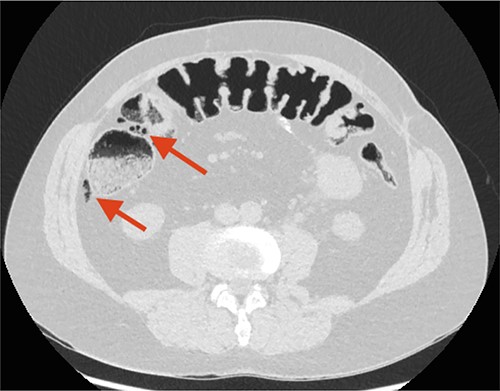

Three weeks later, a CT urography showed FIA, but the patient still had no symptoms indicative of peritonitis. Three months later, a CT scan showed progression of FIA and air bubbles in the wall of the ascending colon (Fig. 3).

CT scan performed 3 months after the first admission to the ED. The arrow points at increased FIA and air bubbles in the colonic wall as signs of Pneumatosis cystoides Intestinalis, PCI.

Pneumatosis cystoides intestinalis (PCI) was suspected.

Retrospectively, the two initial CT scans were reviewed with an independent radiologist, and gas-filled cysts were located in the wall of the ascending colon, representing PCI on both CT scans.